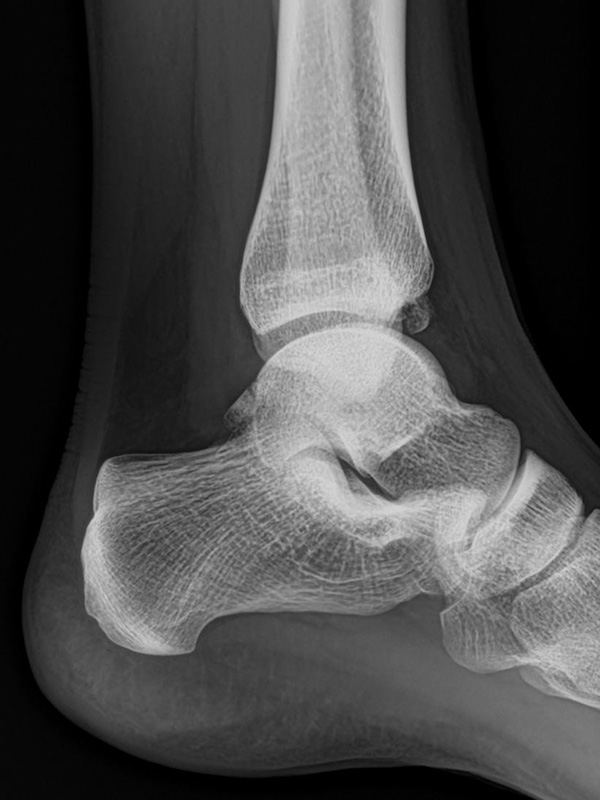

Sprunggelenk lateral ohne Belastung

Positionierung:

• Patient liegt auf dem Rücken und dreht den Fuß des aufzunehmenden Beins so nach innen, dass beide Malleolen genau übereinanderstehen.

• Die laterale Fuss-Seite liegt auf der Kassette, das Sprunggelenk ist 90° angewinkelt.

• Der Zentralstrahl wird zentral auf das Sprunggelenk gerichtet.

Kennzeichen des Röntgenbildes:

• Oberes und unteres Sprunggelenk sind rein seitlich abgebildet, inklusive Kalkaneus.

• Die Malleolen kommen übereinander zu liegen.

• Tibiagelenkfläche und Talusrolle werden exakt seitlich dargestellt, es kommt zu keinen Doppelkonturen.

• Die Fibula projiziert sich ins mittlere bis hintere Drittel der Tibiagelenkfläche.

• Die vordere und hintere Tibiakante, das Chopart-Gelenk und das Subtalargelenk kommen zur Darstellung.

• Das proximale Ende des Os metatarsale V ist mit abgebildet.

• Der Weichteilmantel (Achillessehne) ist erkennbar.

Besondere Bemerkungen zum Beispielbild:

• Patient mit anamnestisch chronischer OSG Instabilität.

• Ventral der Tibia findet sich ein abgebrochener Osteophyt.

Zur Vollansicht und zum Lesen der Bildbeschreibung bitte die Bilder anklicken.